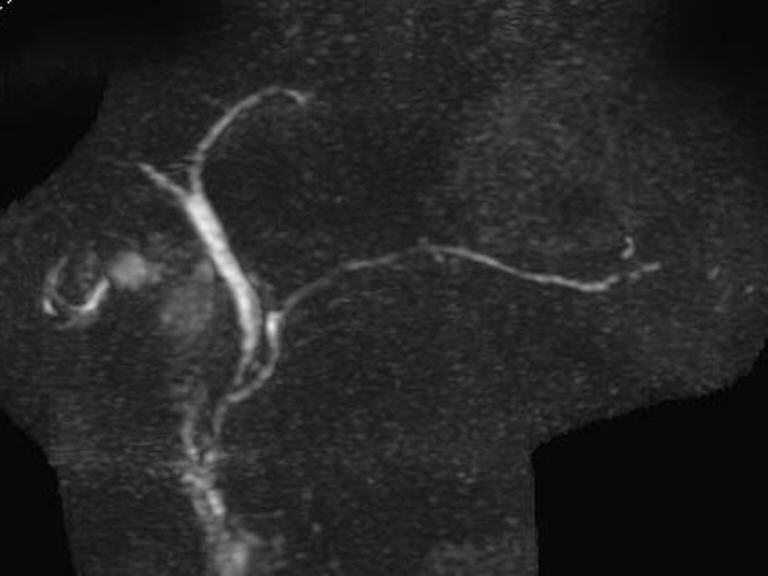

Mit der Magnetresonanz-Cholangiopankreatikographie (MRCP) bieten wir Ihnen eine schonende und strahlungsfreie Methode zur detaillierten Untersuchung der Gallenwege, Gallengänge und Bauchspeicheldrüsengänge. Dieses hochmoderne Verfahren ermöglicht eine klare und präzise Darstellung, ohne dass ein Eingriff oder die Gabe von Kontrastmittel über die Gallenwege erforderlich ist. Wir bieten die MRCP im Rahmen einer umfassenden Untersuchung der Leber und Bauchspeicheldrüse an.

- Exzellente Bildqualität: Detaillierte Darstellung von Gallen- und Bauchspeicheldrüsengängen.

- Früherkennung von Erkrankungen: Erkennt Engstellen, Steine oder andere Veränderungen zuverlässig. Auch Erkrankungen der Leber und der Bauchspeicheldrüse werden sicher erkannt.